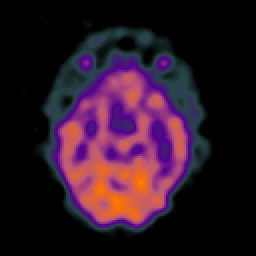

SPECT TC Study #5 -- Slice #22

[Home][Help][Clinical][Tour 1][Tour 2][Tour 3] Slice 22